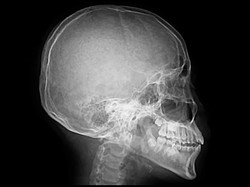

Yasser Al Shahrani Cedera Kepala Akibat Benturan 'Horor' Saat Lawan Argentina

Kondisi pesepakbola Arab Saudi Yasser Al Shahrani dikabarkan kritis setelah cedera yang dideritanya akibat berbenturan saat berlaga dengan Argentina.